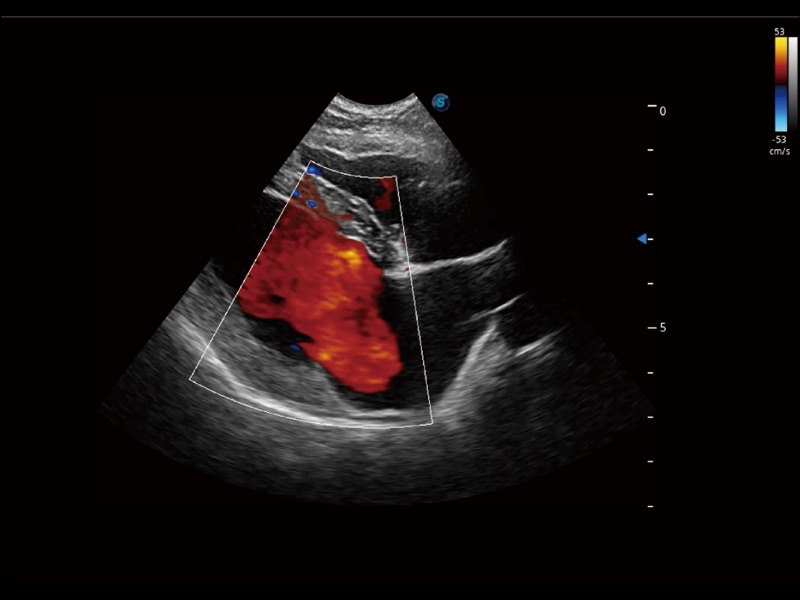

能够基于左心室壁追踪和辛普森法,自动计算射血分数,支持多个可移动点描迹,与手动测量相比,极大节省了动物医生的时间和精力。

通过360度任意调节3条M型取样线,在同一心动周期上观察心脏不同位置的运动曲线,得到准确的心功能测量数据,有效评估心肌运动及左心室功能。

实时用颜色表示心肌组织运动,观察和定量组织的运动情况,对快速检测与评估心肌的灌注和活性、电传导及心肌收缩和舒张功能等均能提供重要的诊断信息。

当心脏测量结果超出正常范围时,可实时预警提示动物医生,减少疾病漏诊概率。